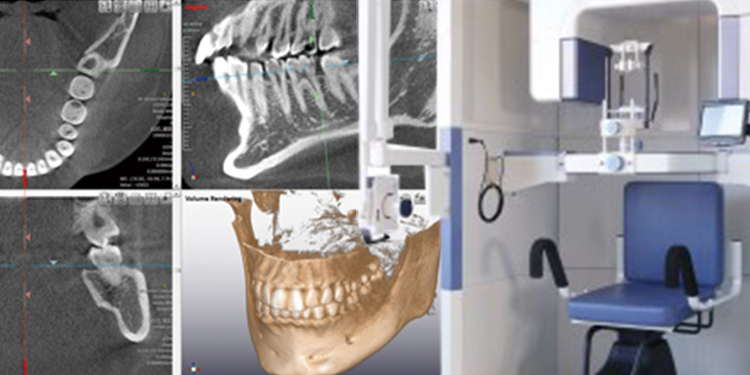

歯科用CTスキャン

歯根からの精密な治療を実現

歯科用CTは、通常のレントゲンとは違い、3次元で歯の状態を解析できます。

矯正治療でも、歯科用CTのデータを口腔内スキャンデータと統合し、歯根の動きまでしっかりと計算しながら治療を進めます。